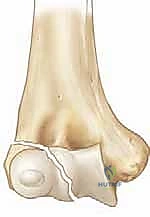

The distal fragment we are tasked with reducing typically retains robust and clinically significant soft tissue attachments. The origins of the Extensor Carpi Radialis Longus (ECRL), Extensor Carpi Radialis Brevis (ECRB), and the supinator muscle exert a continuous distal and rotational pull on the fragment. Furthermore, the Lateral Collateral Ligament (LCL) complex—comprising the radial collateral ligament, the annular ligament, and the lateral ulnar collateral ligament (LUCL)—remains firmly attached. This complex provides crucial posterolateral rotatory stability to the elbow.

These retained muscular and ligamentous attachments are a double-edged sword. Mechanically, they make the fragment highly resistant to closed reduction maneuvers and predispose it to severe rotational displacement, often flipping the articular surface out of the joint entirely. However, biologically, these attachments are the sole lifeline of the fragment. The blood supply to the lateral condyle enters predominantly through its posterior non-articular surface via vessels running within these soft tissue attachments.

The anterior aspect of the fracture is meticulously exposed. A periosteal elevator or a Freer elevator is used to gently sweep the anterior capsule and brachialis muscle off the distal humerus to visualize the metaphyseal fracture line and the joint surface. Crucially, no dissection is performed on the posterior aspect of the lateral condyle. The posterior soft tissue attachments must remain completely inviolate to preserve the vascularity of the fragment.

Reduction is achieved by manipulating the fragment using a combination of direct pressure and positioning of the arm. Often, supinating the forearm and applying a gentle varus stress can help unlock the fragment. A sharp dental pick or a small bone tenaculum can be used to carefully manipulate the metaphyseal portion of the fragment. The reduction is judged visually by assessing the articular cartilage anteriorly and the metaphyseal fracture line laterally.

Clinical & Radiographic Imaging Archive